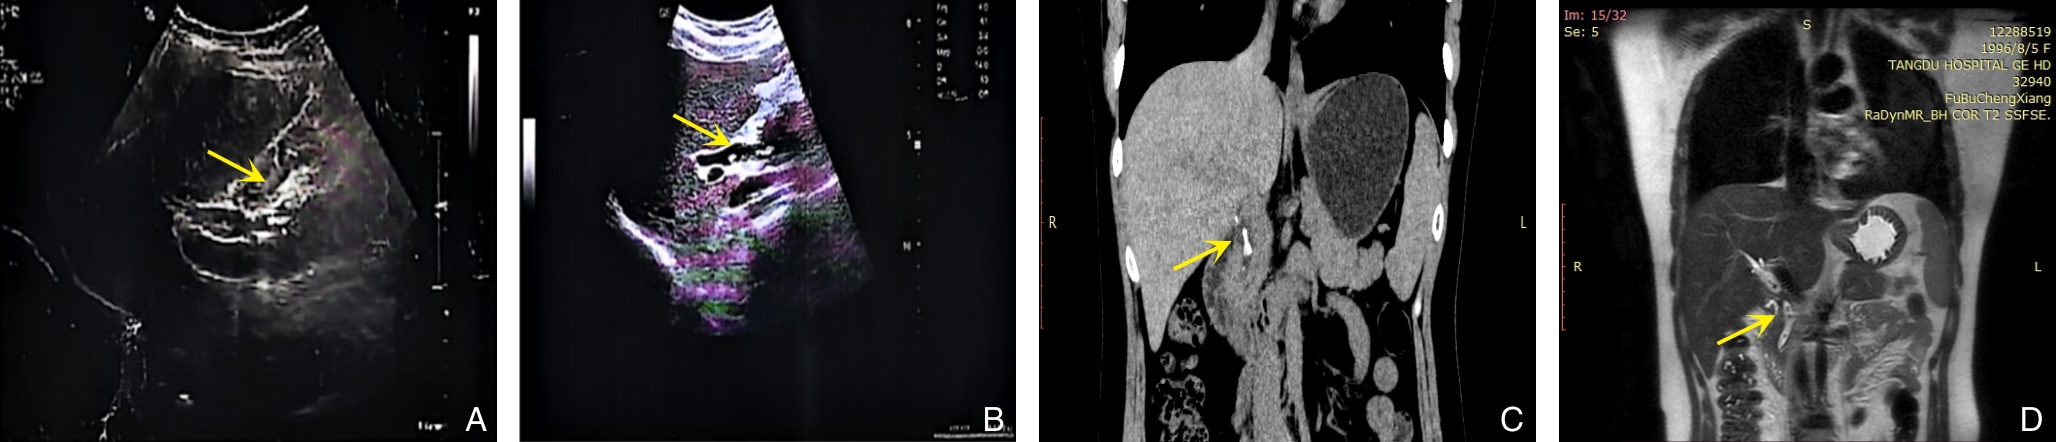

2026, 35(2):391-396. doi: 10.7659/j.issn.1005-6947.250673

摘要:背景与目的 胆总管结石合并壶腹周围癌临床罕见,二者症状重叠,易导致误漏诊并延误治疗。本研究旨在分析其误漏诊特点、原因及优化诊断策略。方法 回顾性分析2022年11月—2025年8月河北医科大学第二医院普外一科收治的9例胆总管结石合并壶腹周围癌误漏诊患者的临床资料,重点总结首诊特征、影像学表现、确诊途径及治疗结局。结果 9例患者均以胆囊结石、胆总管结石为首诊诊断并接受相关治疗,误漏诊时间为35~180 d。初诊多依赖腹部超声及CT,均未发现壶腹部病变。转诊后经增强CT、经内镜逆行胰胆管造影活检或EUS-FNA明确诊断。7例行胰十二指肠切除术,2例行内镜胆道支架置入。随访5~30个月,3例死亡。误漏诊主要与临床表现重叠、对肿瘤警惕性不足、过度依赖常规影像检查及术中探查不充分有关。结论 胆总管结石合并壶腹周围癌易被掩盖,尤其在老年及伴胆管扩张、肿瘤标志物升高患者中应提高警惕。构建“影像筛查-内镜评估-病理确诊”的分层诊断路径,并规范术中探查与术后随访,有助于降低误漏诊率。